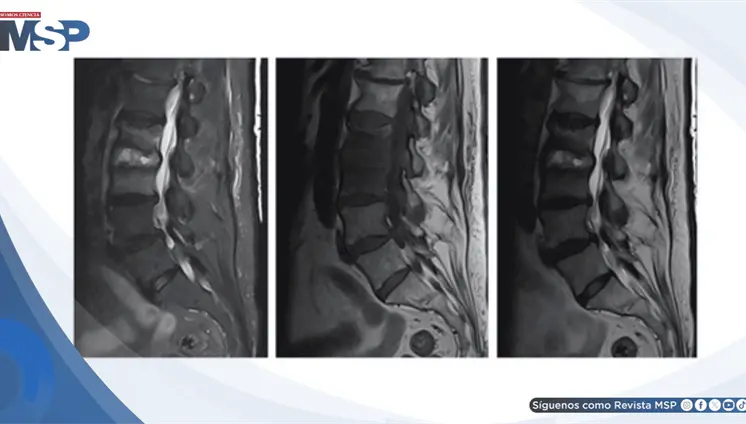

Diagnostican osteomielitis vertebral por SARM tras taponamiento nasal en paciente anticoagulada